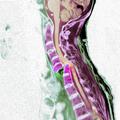

opozorilo Kirurgi svarijo pred neprevidnostjo Ljubljanski kirurgi letno obravnavajo okoli 50 poškodb zaradi neprevidnega skakanja v vodo. Zato pred začetkom kopalne …